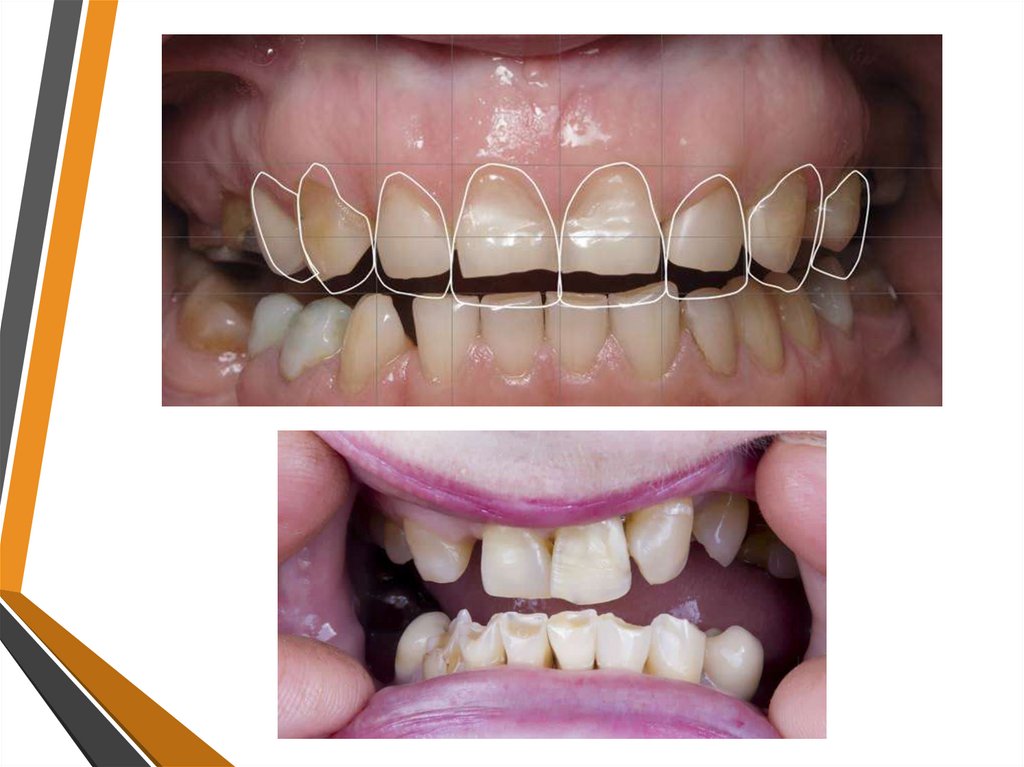

3. КЛИНОВИДНЫЙ ДЕФЕКТ

• Клиновидный дефект — некариозное поражение,

возникающее в твёрдых тканях зубов,

характеризующееся образованием в области шейки

зуба дефекта в виде клина.

• Стадии клиновидного дефекта:

1. Начальные проявления без видимой глазом убыли ткани,

которые выявляются с помощью лупы. Повышена

чувствительность к внешним раздражителям.

2. Поверхностные клиновидные дефекты в виде щелевых

повреждений эмали с той же локализацией вблизи эмалевоцементной границы. Глубина дефекта до 0,2 мм, длина от 3

до 3,5 мм. Характерна гиперестезия шеек зубов.

3. Средние клиновидные дефекты, образованные двумя

плоскостями, располагающимися под углом 40-45°. Средняя

глубина дефекта 0,2 – 0,3 мм, длина 3,5 – 4 мм.

4. Глубокий клиновидный дефект, имеющий длину 5 мм и

более, сопровождающийся поражением глубоких слоёв

дентина вплоть до коронковой полости зуба, что может

завершиться отломом коронки. Дно и стенки гладкие,

блестящие, края ровные.

• Дефекты могут быть единичными, но чаще их несколько,

располагаются на симметричных зубах.

• Обычно поражаются вестибулярные поверхности на

верхней челюсти – 1,4,5 зубов, на нижней челюсти –

1,2,3,4,5 зубов.

• Клиновидные дефекты располагаются в области шеек

зубов, имеют блестящую поверхность, при зондировании

гладкие, плотные, чаще безболезненные.